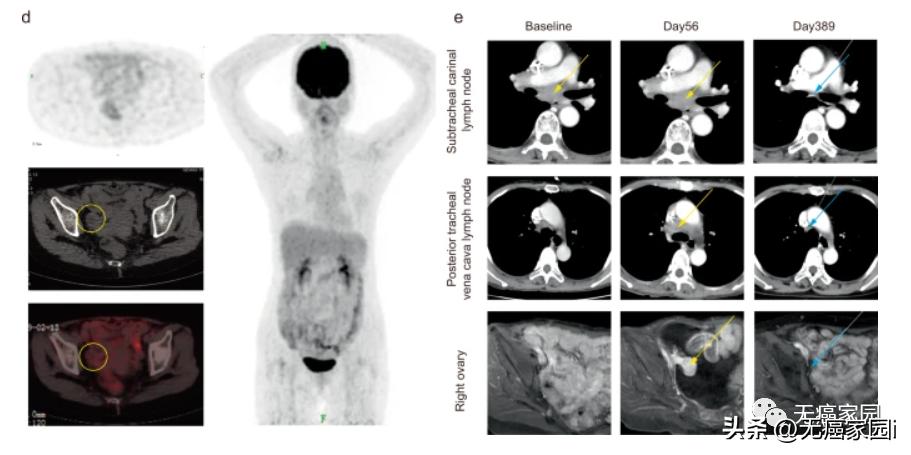

两周后,患者恶性腹水消失,临床影像学检查显示锁骨上淋巴结转移灶体积缩小约30%。 2个月后,所有转移淋巴结的短轴均减小<1 cm, 根据RECIST 指南,患者在这些淋巴结中达到完全缓解 (CR) ,同时, 卵巢种植转移的长径减少了20% (图1c)。

在初次接种疫苗后的第 231 天,通过 PET 扫描评估患者的肿瘤负荷。 并且成像表明所有病变完全消退 (图1d)。 联合治疗期间第389天的CT扫描显示卵巢植入转移也完全消失 (图1e)。 重新分期 CT 显示完全消退仍然存在25个月,直到2021年10月。

d.右侧卵巢的 PET/CT 图像(左图,黄色圆圈)和 PET 图像(右图)显示第231天完全消退。

e.治疗期间靶向肿瘤病变的代表性图像;黄色箭头代表靶向肿瘤病变;蓝色箭头表示完全消退的肿瘤病变。